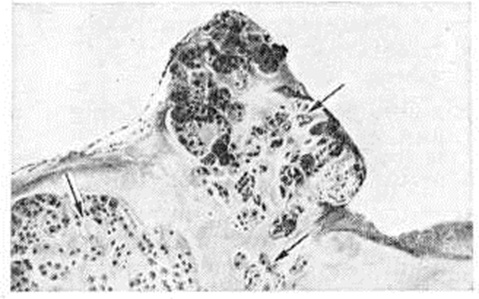

Рис. 1.

Микропрепарат синовиальной оболочки при хондроматозе сустава: стрелками указаны островки хрящевой ткани; окраска гематоксилин-эозином; ×100.

Макроскопически при Хондроматоз суставов ограниченные или обширные участки синовиальной оболочки покрыты узелками и диффузными возвышениями плотной консистенции. Отдельные узелки выступают над поверхностью синовиальной оболочки в виде полипов на ножке. Некоторые из них отшнуровываются и располагаются в полости сустава в виде свободных внутрисуставных телец величиной от нескольких миллиметров до 1—2 сантиметров в диаметре. Внутрисуставные тельца имеют округлую и овальную форму, гладкую поверхность белого или желтоватого цвета. Количество таких телец в суставе может достигать десятков и сотен. При опухолевидной форме Хондроматоз суставов внутрисуставные тела имеют вид крупных (до 3—5 сантиметров в диаметре) бугристых образований, состоящих из сливающихся узлов и долек хрящевой ткани. Микроскопически синовиальная оболочка утолщена, с гиперплазированными ворсинками. В ней отмечается инфильтрация лимфоидными и плазматическими клетками, обусловленная реактивным синовитом (смотри полный свод знаний). Отдельные ворсинки или вся толща синовиальной оболочки содержат очаги хрящевой ткани (смотри полный свод знаний) в виде мелких узелков и островков (рисунок 1). Хондроматозные очаги состоят из межуточного вещества с беспорядочно расположенными в нем хрящевыми клетками. Иногда архитектоника хондроматозных очагов отдалённо напоминает суставной хрящ, реже — хондрому (смотри полный свод знаний). В крупных очагах часто обнаруживают зоны обызвествления (смотри полный свод знаний: Кальциноз) и костеобразования (смотри полный свод знаний: Оссификаты). Могут встречаться очаги, состоящие только из костной ткани, представленной отдельными костными перекладинами или сетью перекладин пластинчатого строения с жёлтым, реже красным, костным мозгом в межбалочных пространствах. Свободные внутрисуставные тельца состоят из гиалинового хряща, реже — из гиалиновой и волокнистой хрящевой ткани. Поверхность внутрисуставных телец покрыта слоем волокнистой соединительной ткани, образующей капсулу. Иногда эта ткань напоминает перихондр и, видимо, служит источником образования хрящевого вещества. Обызвествление наблюдается в форме очагов или полос, что указывает на периодичность отложения солей кальция.